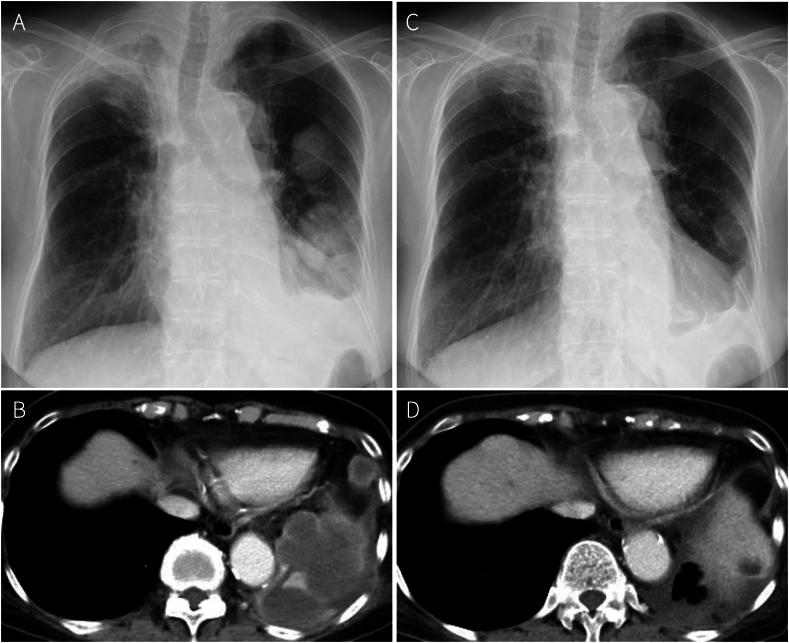

Pulmonary pleomorphic carcinoma (PPC) is a rare and aggressive lung malignancy with limited treatment options. While immune checkpoint inhibitors (ICIs) have shown promise in treating PPC, evidence regarding their efficacy in epidermal growth factor receptor ()-mutated cases remains scarce. We report a case of a woman in her 70s diagnosed with PPC harboring L858R + E709K mutations and high expression (95 %) of programmed death-ligand 1 (PD-L1). After relapsing from concurrent chemoradiotherapy for a Pancoast tumor, the patient received osimertinib as second-line therapy. Despite an initial response, rapid disease progression necessitated left lower lobectomy, confirming PPC diagnosis. Subsequent treatment with pembrolizumab achieved notably tumor response. Although Grade 3 immune-related colitis developed, it was successfully managed with prednisolone, allowing completion of six courses of pembrolizumab. This case demonstrates the potential efficacy of ICIs in -mutated PPC, even after epidermal growth factor receptor -tyrosine kinase inhibitor (EGFR-TKI) failure and highlights the importance of appropriate adverse event management. Our findings suggest that ICIs may be a viable treatment option for -mutated PPC patients, particularly those with high PD-L1 expression.

肺多形性癌(PPC)是一种罕见且侵袭性强的肺恶性肿瘤,治疗选择有限。虽然免疫检查点抑制剂(ICI)在治疗PPC方面已显示出前景,但关于其在表皮生长因子受体(EGFR)突变病例中的疗效证据仍然稀少。我们报告了一例70多岁女性,诊断为携带L858R + E709K突变且程序性死亡配体1(PD-L1)高表达(95%)的PPC。在针对潘科斯特瘤的同步放化疗后复发,患者接受奥希替尼作为二线治疗。尽管最初有反应,但疾病迅速进展需要进行左下叶切除术,确诊为PPC。随后使用帕博利珠单抗治疗取得了显著的肿瘤反应。尽管出现了3级免疫相关结肠炎,但通过泼尼松龙成功控制,使帕博利珠单抗能够完成六个疗程。该病例证明了ICI在EGFR突变的PPC中的潜在疗效,即使在表皮生长因子受体酪氨酸激酶抑制剂(EGFR-TKI)治疗失败后,并强调了适当管理不良事件的重要性。我们的研究结果表明,ICI可能是EGFR突变的PPC患者的一种可行治疗选择,特别是那些PD-L1高表达的患者。